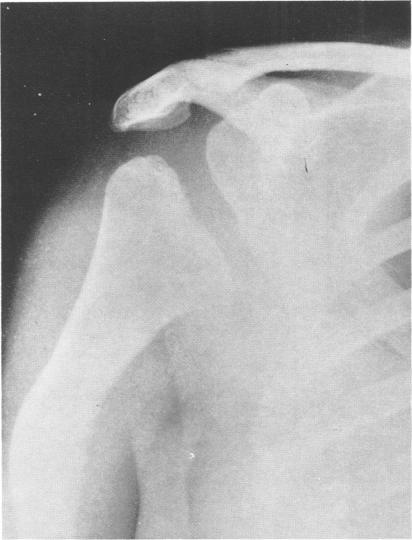

This survey reviews the diagnosis (predominantly radiological) of 32 cases of pseudoachondroplasia from 26 kindreds and illustrates the natural history and varying appearance of the disordered bone growth from infancy to adult life. In addition, an attempt has been made to detect phenotypic differences between autosomal dominant and recessive types (excluding isolated cases), analysing 10 kindreds of dominant inheritance (three in the current survey, seven from published reports) and six of recessive inheritance (three in the current survey, three from published reports). There appears to be no clinical or radiographical feature which clearly distinguishes them, but, using height as a criterion of severity, among those with autosomal recessive inheritance there was a disproportionate number of the most severely affected cases and there also appears to be very little intrafamilial variation. It is possible that pseudoachondroplasia can be subdivided into autosomal dominant mild and severe and autosomal recessive mild and severe, but full delineation must await elucidation of the basic defect at biochemical and molecular levels.

本调查回顾了来自26个家族的32例假软骨发育不全病例的诊断(主要是放射学诊断),并阐述了该疾病从婴儿期到成年期骨骼生长紊乱的自然病史及不同表现。此外,还尝试检测常染色体显性和隐性类型(不包括散发病例)之间的表型差异,分析了10个显性遗传家族(本次调查中有3个,已发表报告中有7个)和6个隐性遗传家族(本次调查中有3个,已发表报告中有3个)。似乎没有能明确区分它们的临床或影像学特征,但是,以身高作为严重程度的标准,在常染色体隐性遗传患者中,受影响最严重的病例比例过高,而且家族内差异似乎也很小。假软骨发育不全有可能可细分为常染色体显性轻度和重度以及常染色体隐性轻度和重度,但要进行全面分类,必须等待在生化和分子水平上阐明其基本缺陷。